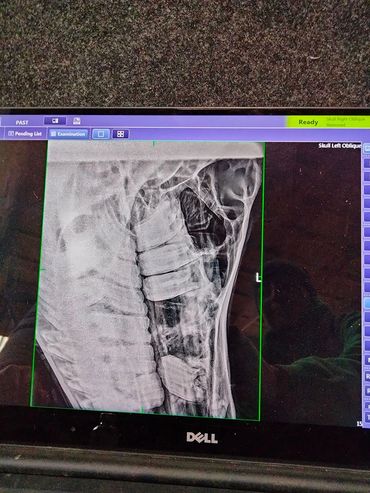

First two pictures are from November 29 and the other two are from December 11 when she had the emergency:

Stella saw the vet a couple of times. On November 29,2021 Dr. Lauren too another look at Stella because we are still fighting her sinus infection and neither of the antibiotics SMZ or Enro were able to get rid of it. Dr. Lauren took more x-rays to look at her sinus. Because none of the meds worked we did a culture to see which antibiotics would be best to get rid of the bacteria. Turns out those bacterias are the hardest ones to get rid off.

Stella had her surgery done today. Everything went well. The vet decided during surgery to only pull the two teeth on the left side because there was no indication of an infection on the right side of her sinuses. The tube to flush her sinus was also placed on the left and rinsed through. The vet is going to repeat that a few more times. He also stitched up that hole on her face sitting on the left side of her sinuses.